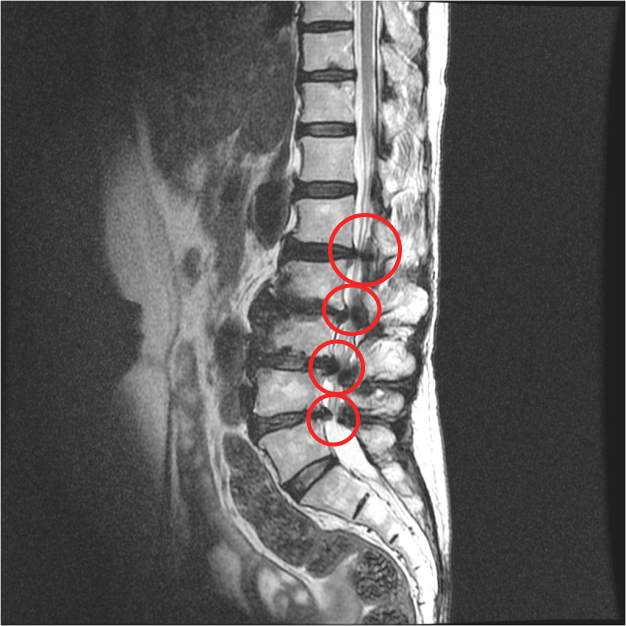

그런데, 보시면 협착증은 이 부분만이 아니라 주변 부분도 다 퇴행되어 있습니다. 그래서 고정술을 한 이후에 이 부분이 구부리지도 펴지도 못하게 되기 때문에 이미 퇴행된 주변 마디에 부담을 주게 됩니다. 주변 마디가 더 많이 구부렸다 폈다가 해줘야 하는 것이죠. 그런데 앞서 말했듯이 협착증 환자는 이미 주변 위아래 마디도 퇴행되어 약해진 상태인데, 추가적으로 부담을 주니까 시간이 흐르면 주변 부위도 문제가 생기게 되는데요. 이것을 인접분절질환이라고 합니다. 일반적으로 척추유합술 후 이러한 문제가 많이 발생하기 때문에 인접분절질환이라는 이름까지 만들어져 있습니다. 이러한 인접분절질환은 특히 수술 후 관리를 잘 못하면 당연히 더 잘 생기기 때문에 유합술을 했다면, 이 인접분절질환이 생기지 않도록 관리를 세심하게 잘 해줘야 합니다.